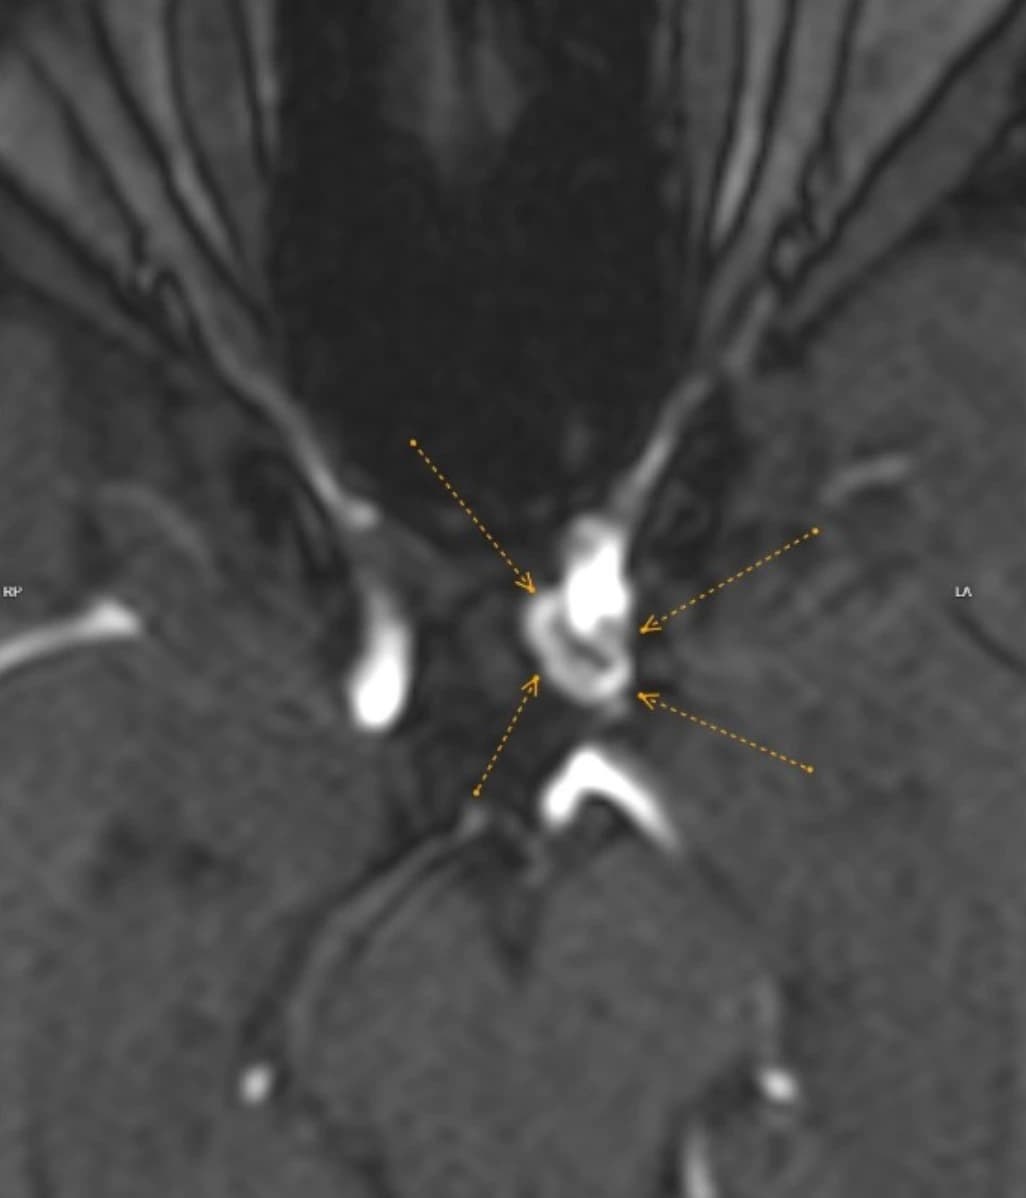

Lynn's 2024 Full-Body MRI identified a 9mm saccular aneurysm at the left internal carotid artery, a finding classified as severe, with neurosurgical and neurointerventional consultation strongly recommended immediately.

A 9mm aneurysm at this location carries an elevated rupture risk, and Lynn's radiologist noted that the MRA and T2-weighted sequences captured were sufficient to initiate the full consultation process without delay, moving her directly into specialist care.

Two years later, Lynn returned to TrueScan for her follow-up Full-Body MRI. Her 2026 report confirmed that she had undergone successful endovascular coiling of the aneurysm, and today's MRA showed no discernible residual or blood flow within the aneurysm sac.

Her radiologist compared the pre-coiling and post-coiling images side by side in the report, confirming stability and recommending continued surveillance per her neurosurgeon's protocol.